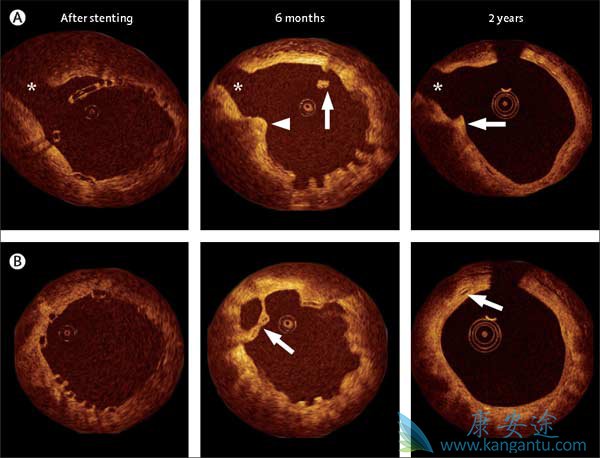

雅培的新型生物吸收性依维莫司洗脱支架或BVS由两层可生物降解的聚合物组成:一种含有免疫抑制剂依维莫司,另一种形成更持久的骨架。随着时间的推移,身体分解并吸收聚合物,最终不会留下任何东西。对于其初始试验运行,将支架置于仅具有单个狭窄或阻塞的动脉的患者中。根据本月在“柳叶刀”上发表的研究,两年后,支架似乎几乎完全被吸收,没有发生心脏死亡,没有已知的支架血栓形成,也没有证据表明动脉已经开始缩窄。

新西兰慈善和奥克兰市立医院的柳叶刀研究主任研究员兼首席研究员约翰·奥米斯顿(John Ormiston)说:“支架实际上似乎停止了缩窄的工作,它是安全的,它消失了。“我们希望血栓形成的长期机会非常低。”

因为金属支架已被证明是如此有效,有些问题是生物吸收型是否值得研究投入,特别是因为证明安全性和有效性的标准设置得如此之高,并且由于还没有证明消失的支架不能留下疤痕的组织。但Ormiston和Stone指出,他们的病人的动脉似乎恢复了弹性,而且与金属不同,侵蚀支架不能阻止新血管的分支。此外,他们注意到患者经常需要返回第二个支架放置 - 如果第一个支架被吸收,它不能妨碍第二次手术。